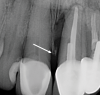

Fig 4. Radiograph of teeth Nos. 8 and 9. After tooth No. 9 is extracted, the height of the papilla will depend on the height of the bone on the mesial side of tooth No. 8, not the implant side of an interdental area. The arrow indicates the mesial osseous crest on tooth No. 8.

Figure 4